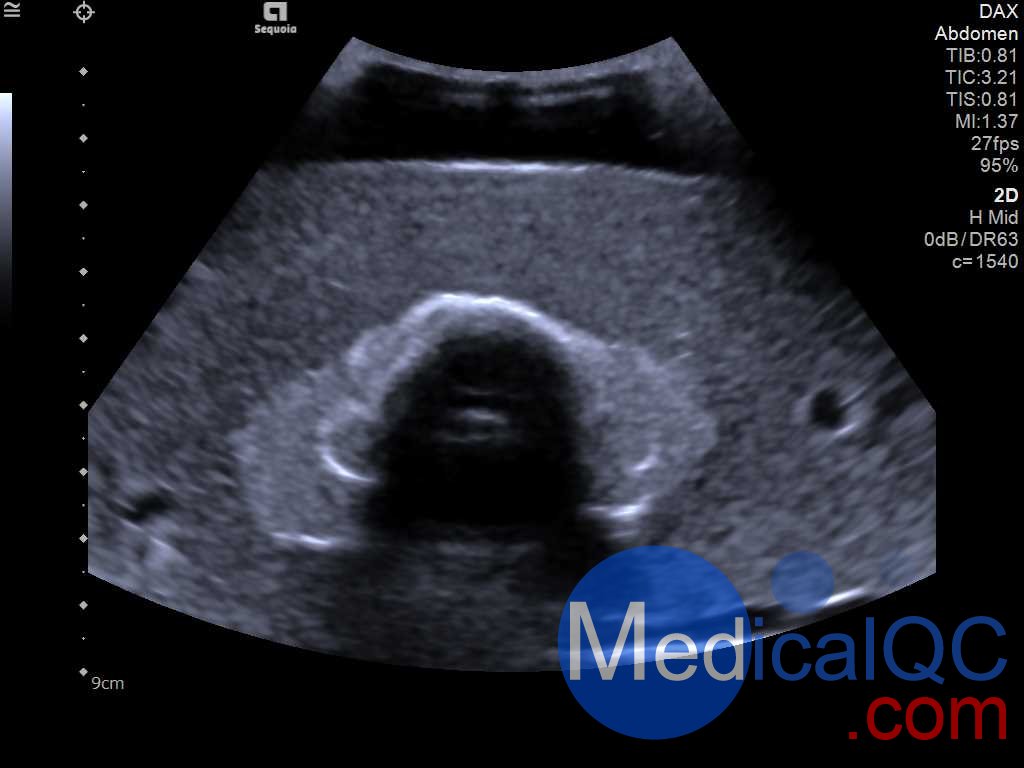

Cirs074甲狀腺超聲訓練模體,Cirs074甲狀腺穿刺模體超聲成像圖:

Cirs074甲狀腺超聲訓練模體,Cirs074甲狀腺穿刺模體超聲成像圖